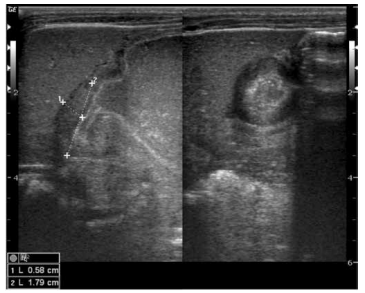

Mãe relata que lactente de 2 meses, alimentando-se exclusivamente de leite materno, vem

apresentando quadro clínico de vômitos em jatos,

não-biliosos, sem ganho de peso, com sinais

de irritação após a amamentação. Ao exame

físico encontra-se levemente desidratado +/+4,

anictérico, acianótico, com pequeno abaulamento

e massa palpável no quadrante superior direito.

Pediatra solicitou exame laboratoriais e avaliação

por imagem.

Considerando o quadro clínico e o exame de imagem, pode-se afirmar que:

Considerando o quadro clínico e o exame de imagem, pode-se afirmar que: